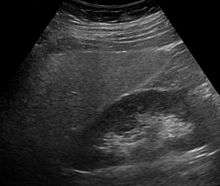

Imaging studies are often obtained during the evaluation process. Ultrasonography reveals a "bright" liver with increased echogenicity. Medical imaging can aid in diagnosis of fatty liver; fatty livers have lower density than spleens on computed tomography (CT), and fat appears bright in T1-weighted magnetic resonance images (MRIs). No medical imagery, however, is able to distinguish simple steatosis from advanced NASH. Histological diagnosis by liver biopsy is sought when assessment of severity is indicated.